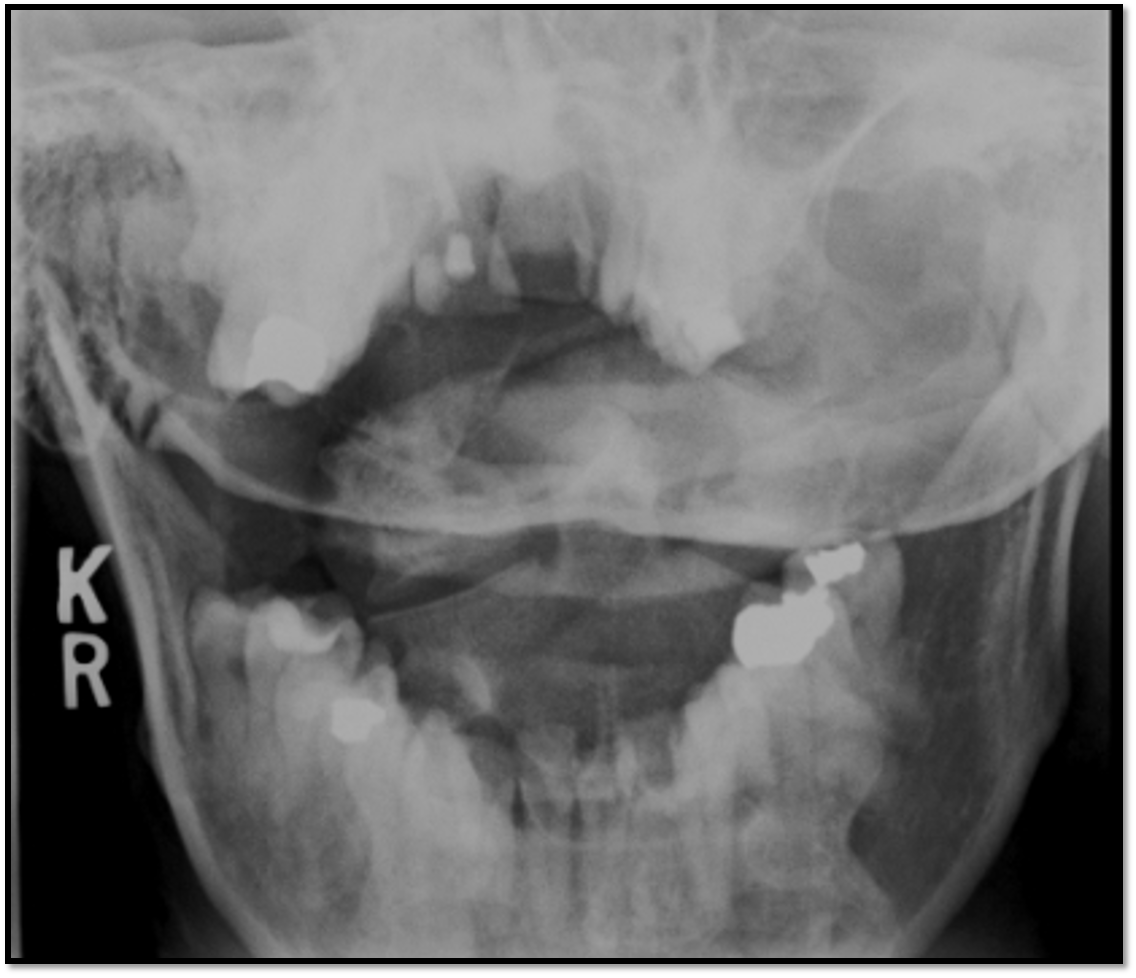

Odontoid Image Criteria

A

• equal distance between dens and lateral masses

• upper incisors aligned with base of skull

• must see lateral edges of C1 and C2

• need to tuck chin

• nose is slightly rotated to the right